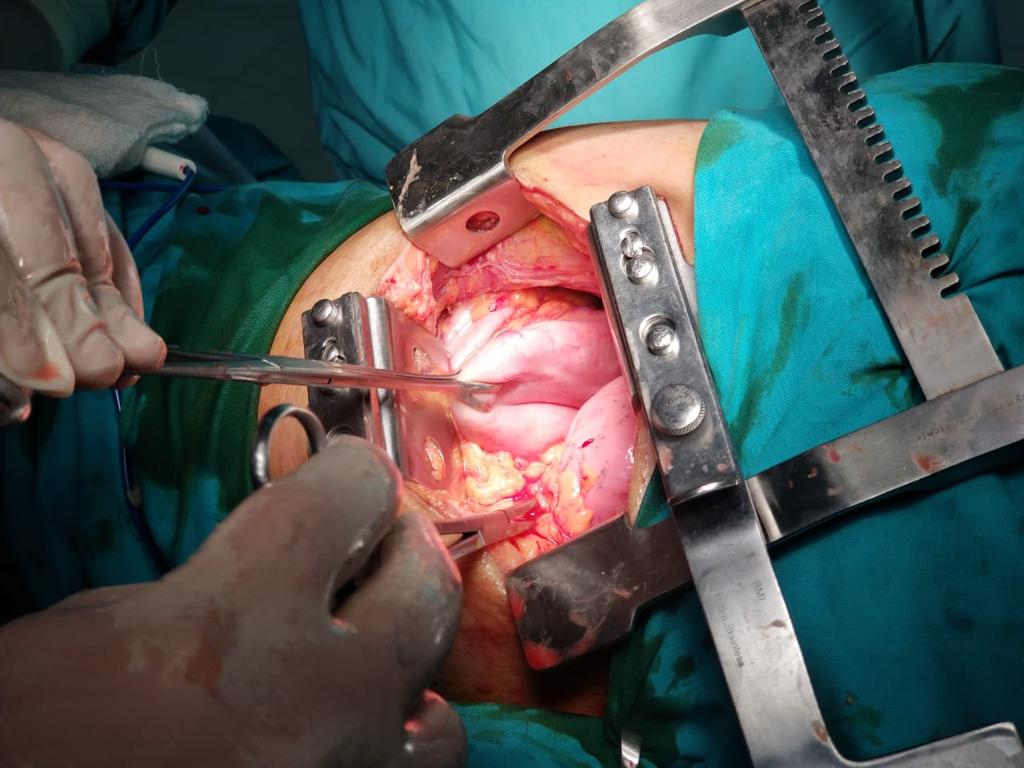

Figure 5. Diaphragmatic defect repaired using Prolene suture in three layers. Lung expanded completely after repair.

The patient was urgently taken to the operation theater and a left posterolateral thoracotomy incision was placed. After dividing the subcutaneous fat and muscle, the seventh intercostal space was entered. Contents of the hernia were visualized in the chest cavity and were manually reduced using digital compression. A loop-shape defect measuring approximately 15 cm in length was identified in the anterolateral part of the muscular portion of the diaphragm. The defect was repaired in three layers using a Prolene® 1 suture in a continuous fashion.

The lung was expanded using valsalva maneuvers. Two chest drains were placed and a routine closure of the chest was performed. The patient was extubated and shifted to the intensive care unit for postoperative care. Twenty-four hours later, she was transferred to the ward. The authors removed the chest drains on the second postoperative day. The patient was discharged home on the third postoperative day. Her postoperative recovery was smooth and uneventful.